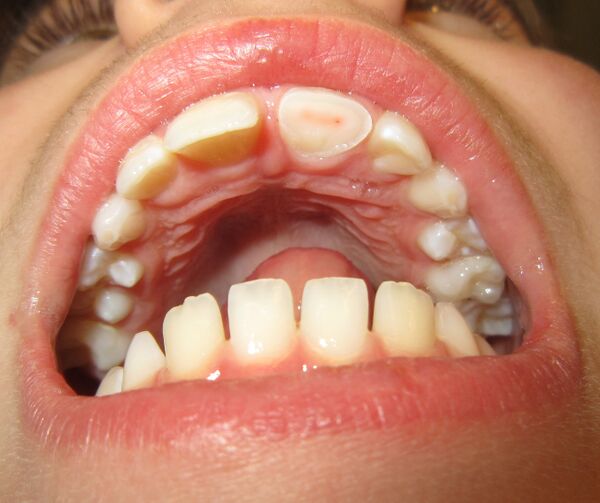

Во временном прикусе (молочные зубы) присутствует 8 резцов, 4 клыка и 8 моляров — всего 20 зубов. У детей они начинают прорезаться в возрасте от 3 месяцев. В период от 6 до 13 лет молочные зубы постепенно заменяются постоянными.

Постоянный прикус состоит из 8 резцов, 4 клыков, 8 премоляров и 8—12 моляров. В редких случаях наблюдаются дополнительные, сверхкомплектные зубы (как молочные, так и постоянные)[1]. Отсутствие третьих моляров, называемых «зубами мудрости» является нормой, а сами третьи моляры увеличивающимся числом учёных уже считаются рудиментом, но это на данный момент спорный вопрос.

- Молочные зубы - временные, выпадают в детском возрасте

- Постоянные зубы - заменяют первоначальные, временные

Развитие зубов у эмбриона человека начинается примерно на 7 неделе. В области будущих альвеолярных отростков возникает утолщение эпителия, который начинает врастать в виде дугообразной пластинки в мезенхиму.[2] Далее эта пластинка разделяется на переднюю и заднюю, в которой формируются зачатки молочных зубов. Зубные зачатки постепенно обосабливаются от окружающих тканей, а затем в них появляются составные части зуба таким образом, что клетки эпителия дают начало эмали, из мезенхимальной ткани образуются дентин и пульпа, а из окружающей мезенхимы развивается цемент и корневая оболочка.

Приблизительно в 6 - 8 месяцев начинает прорезываться центральный нижний резец. За нижними резцами следуют верхние резцы, за ними - клыки и, наконец, моляры. В возрасте от двух с половиной до трёх лет этот процесс завершается. У ребёнка образуется полный комплект из 20 молочных зубов, в каждом ряду - 4 резца, 2 клыка и 4 моляра.

В 6 лет резцы заменяются постоянными зубами, появляются постоянные первые моляры. Приблизительно в 9 лет клыки также заменяются на постоянные зубы. В 12 появляются вторые постоянные моляры, а молочные моляры окончательно заменяются на премоляры. Наконец, в 18 появляются третьи моляры - зубы мудрости.

Время прорастания всех зубов может значительно отличаться. Например, у 25% людей зубы мудрости не вырастают вовсе. Это вызвано уменьшением челюсти в процессе эволюции. По этой же причине у 50% людей проросшие зубы мудрости оказываются зажатыми (стиснутыми под десной). В таком случае их необходимо удалять.